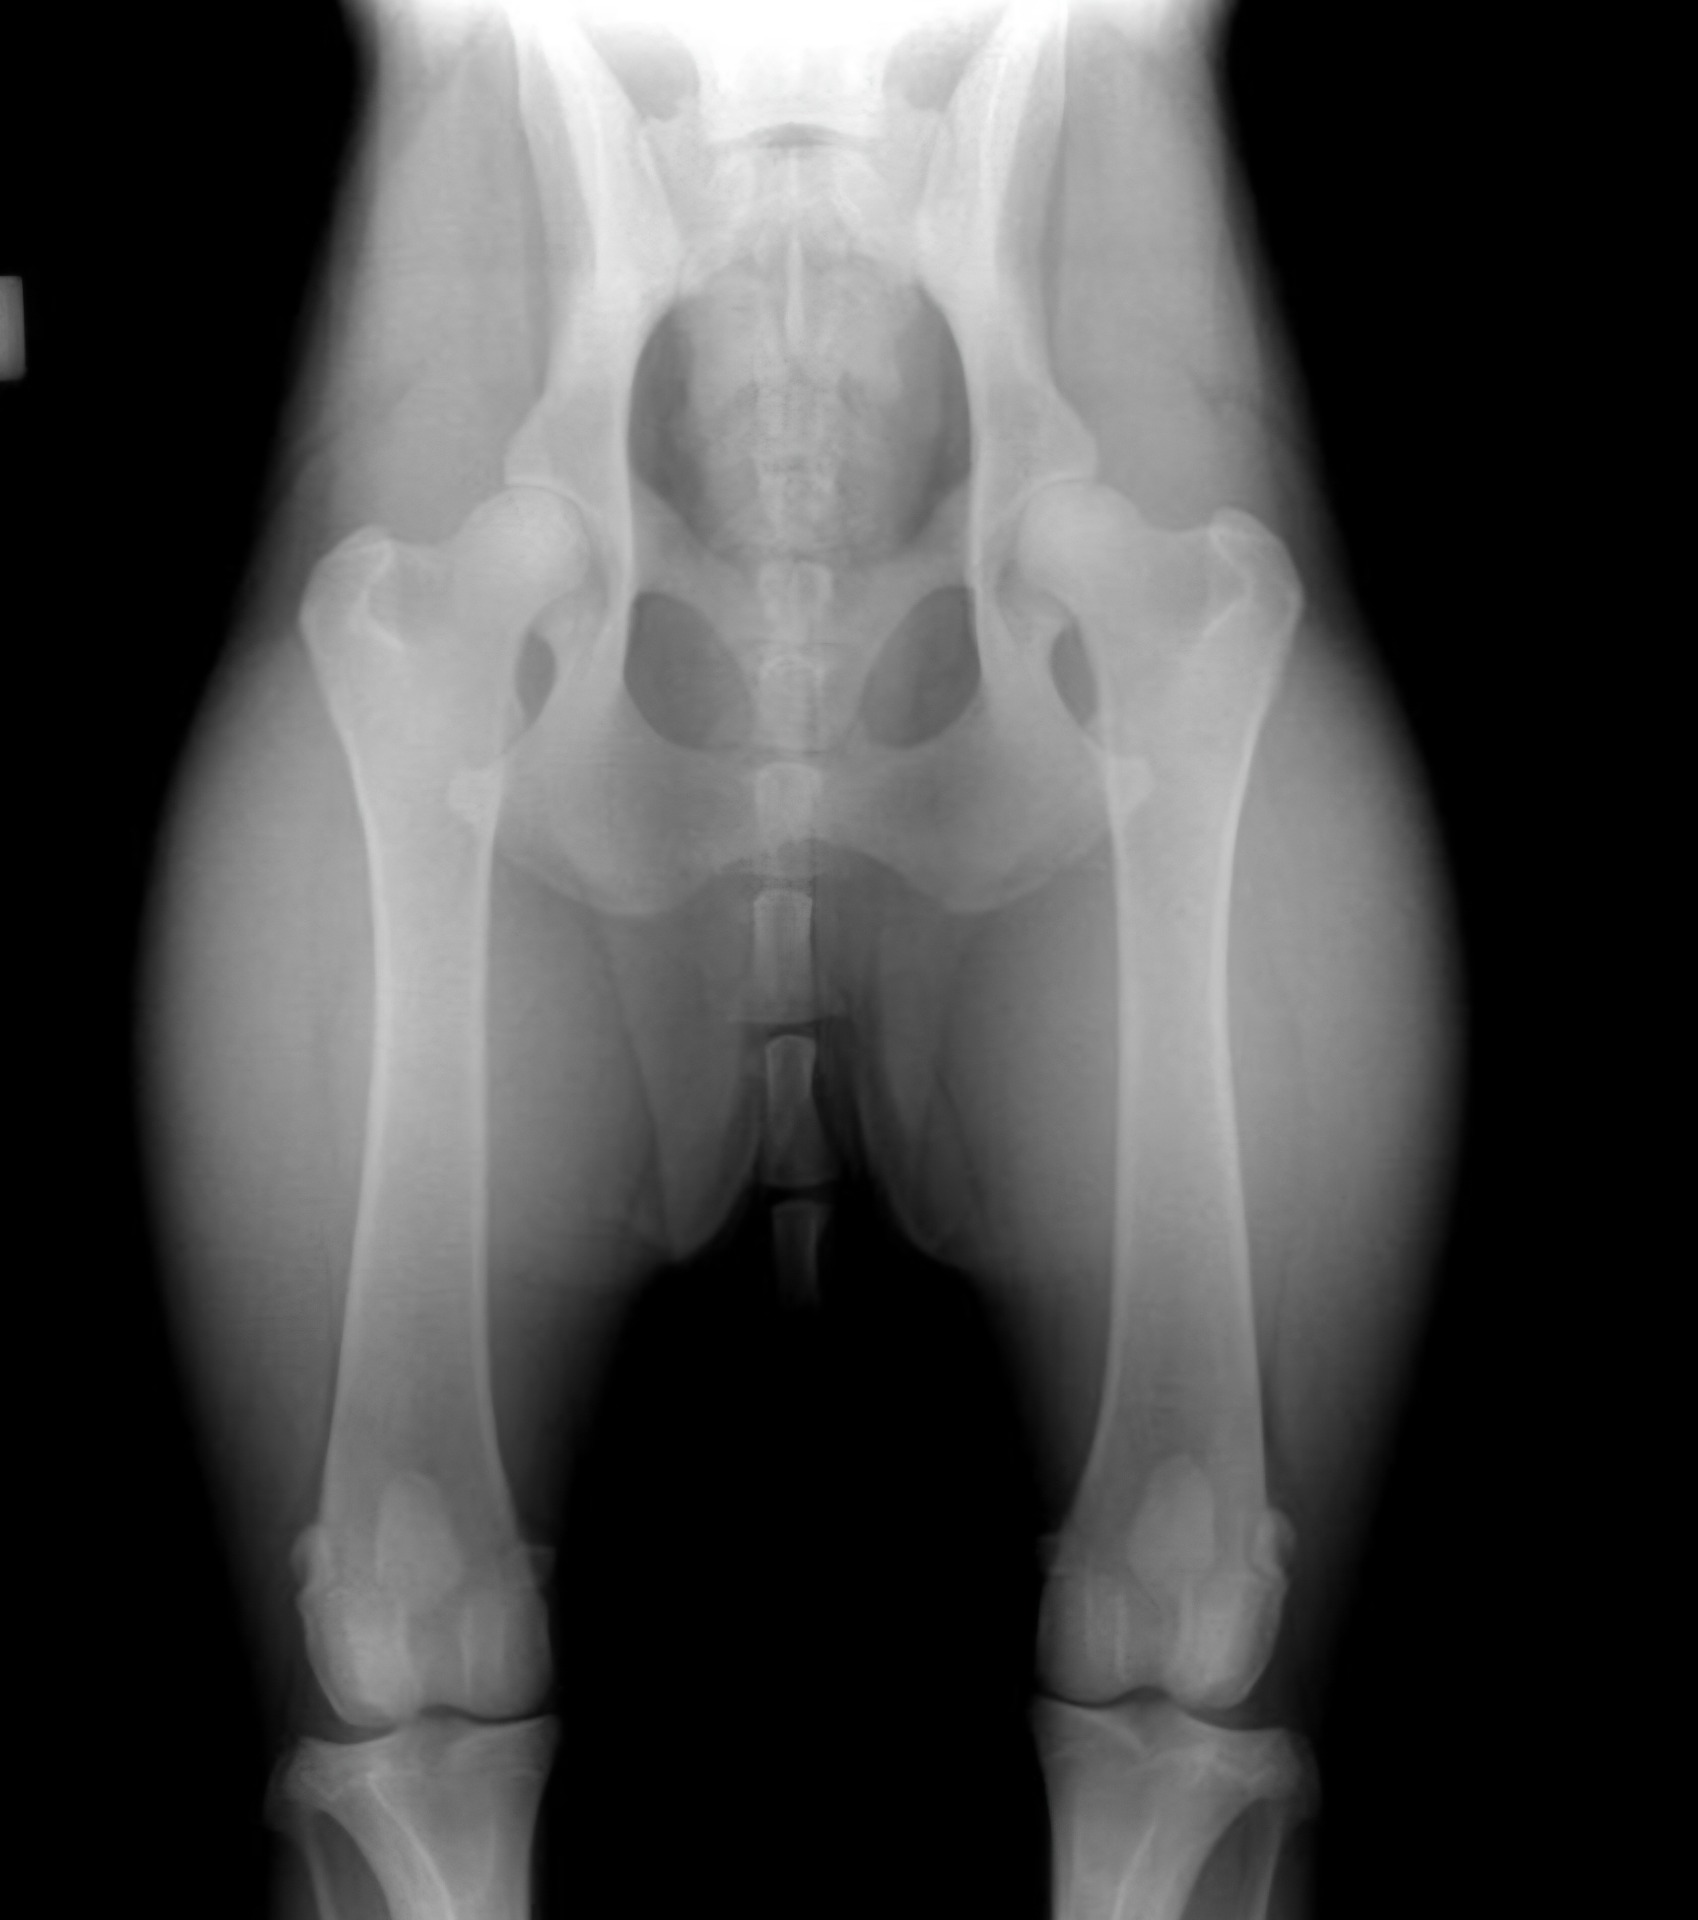

Hofteleddsdysplasi (HD)

Hofteleddsdysplasi er en utviklingsfeil i hofteleddet, der lårhodet (øverst på lårbenet) ikke passer sammen med hofteskåla. Dette kan medføre unormal bevegelighet og slitasje i leddet, slik at leddbrusken slites, og forkalkninger oppstår.

HD utvikles mens hunden vokser, og skyldes en kombinasjon av arv og miljø. Graderingen av HD i NKKs screeningprogram er gjort ut fra røntgenfunn. Hundene må være ferdig utvokst i bekkenet før røntgenbilder kan tas og avleses av NKK. Kun veterinærer som har gyldig avtale med NKK om røntgenfotografering for sentral avlesning, kan få avlest bilder i NKK.